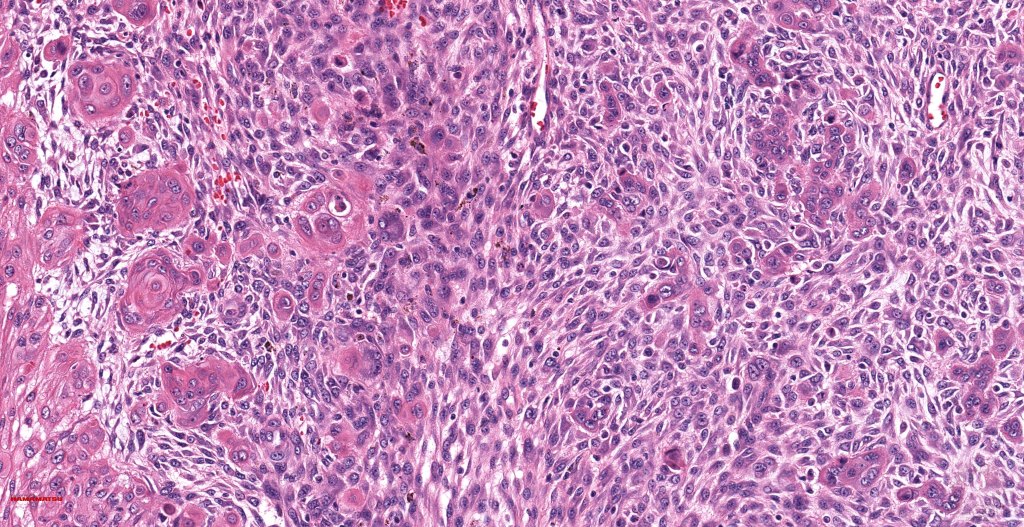

•Biphasic tumor

•Possible epithelial to mesenchymal transition

•Admixture of squamous carcinoma & pleomorphic spindled cell, osteoid, chondroid, MFH-like +/- osteoclast-like giant cells & rarely, smooth muscle, skeletal muscle, myofibroblastic or angiosarcomatous elements